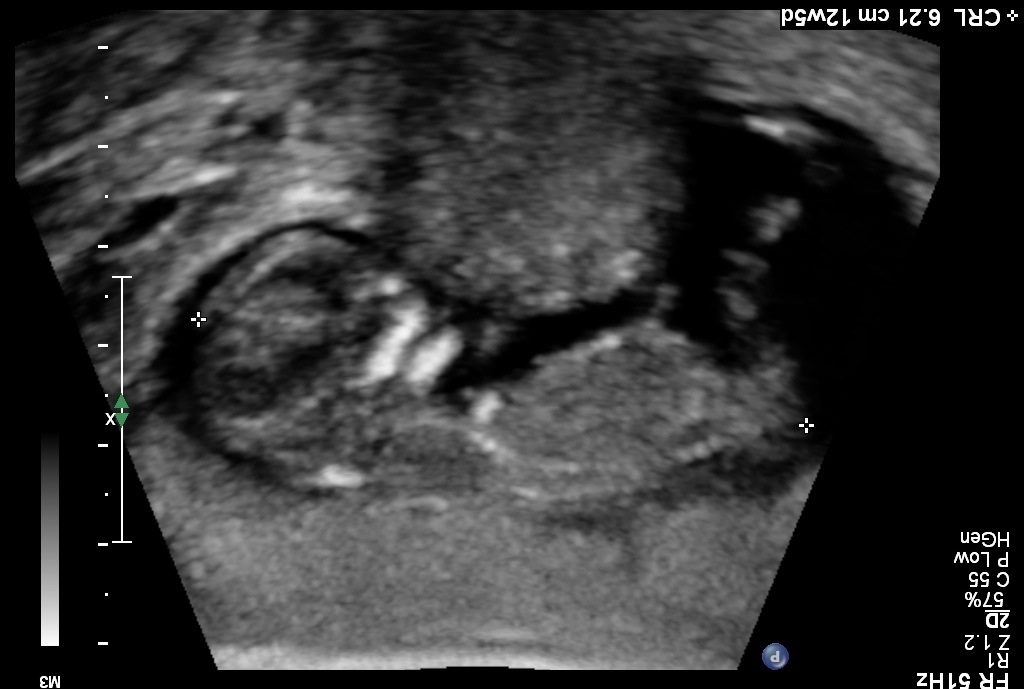

Any chance of posting them the other way up for me:)

Sure let me try...Attachment 12423Attachment 12424Attachment 12425Attachment 12426